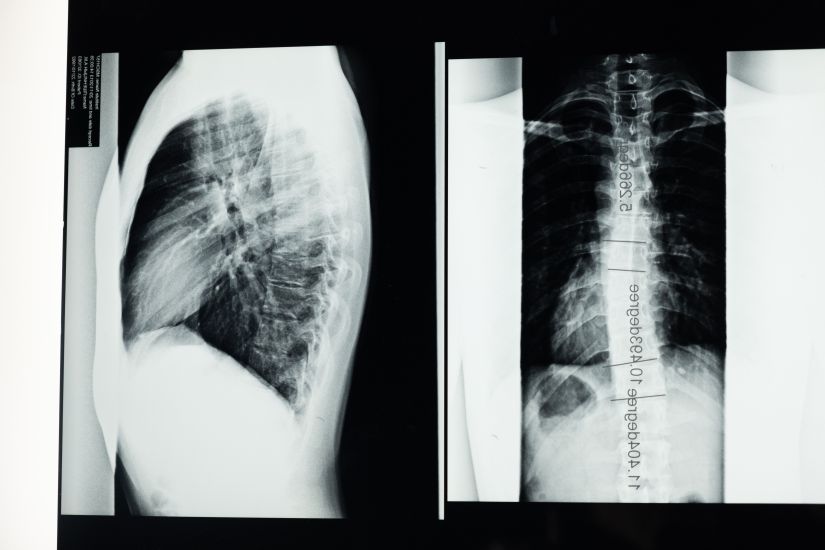

Η σκολίωση είναι μια κοινή πάθηση της σπονδυλικής στήλης που απαντάται συχνά στους εφήβους. Eκατομμύρια νέες περιπτώσεις της πάθησης διαγιγνώσκονται κάθε χρόνο, με την πλειοψηφία τους να αναγνωρίζεται ως ιδιοπαθής σκολίωση – ένας τύπος σκολίωσης που εμφανίζεται σε παιδιά μεταξύ 10 και 12 ετών.

Τα κοινά σημάδια της σκολίωσης περιλαμβάνουν ανομοιόμορφους ώμους ή γοφούς, αλλά γενικά είναι μια ανώδυνη κατάσταση που μπορεί να περάσει απαρατήρητη μέχρι να γίνει κάποια εξέταση ρουτίνας.

Η σκολίωση είναι κληρονομική ασθένεια;